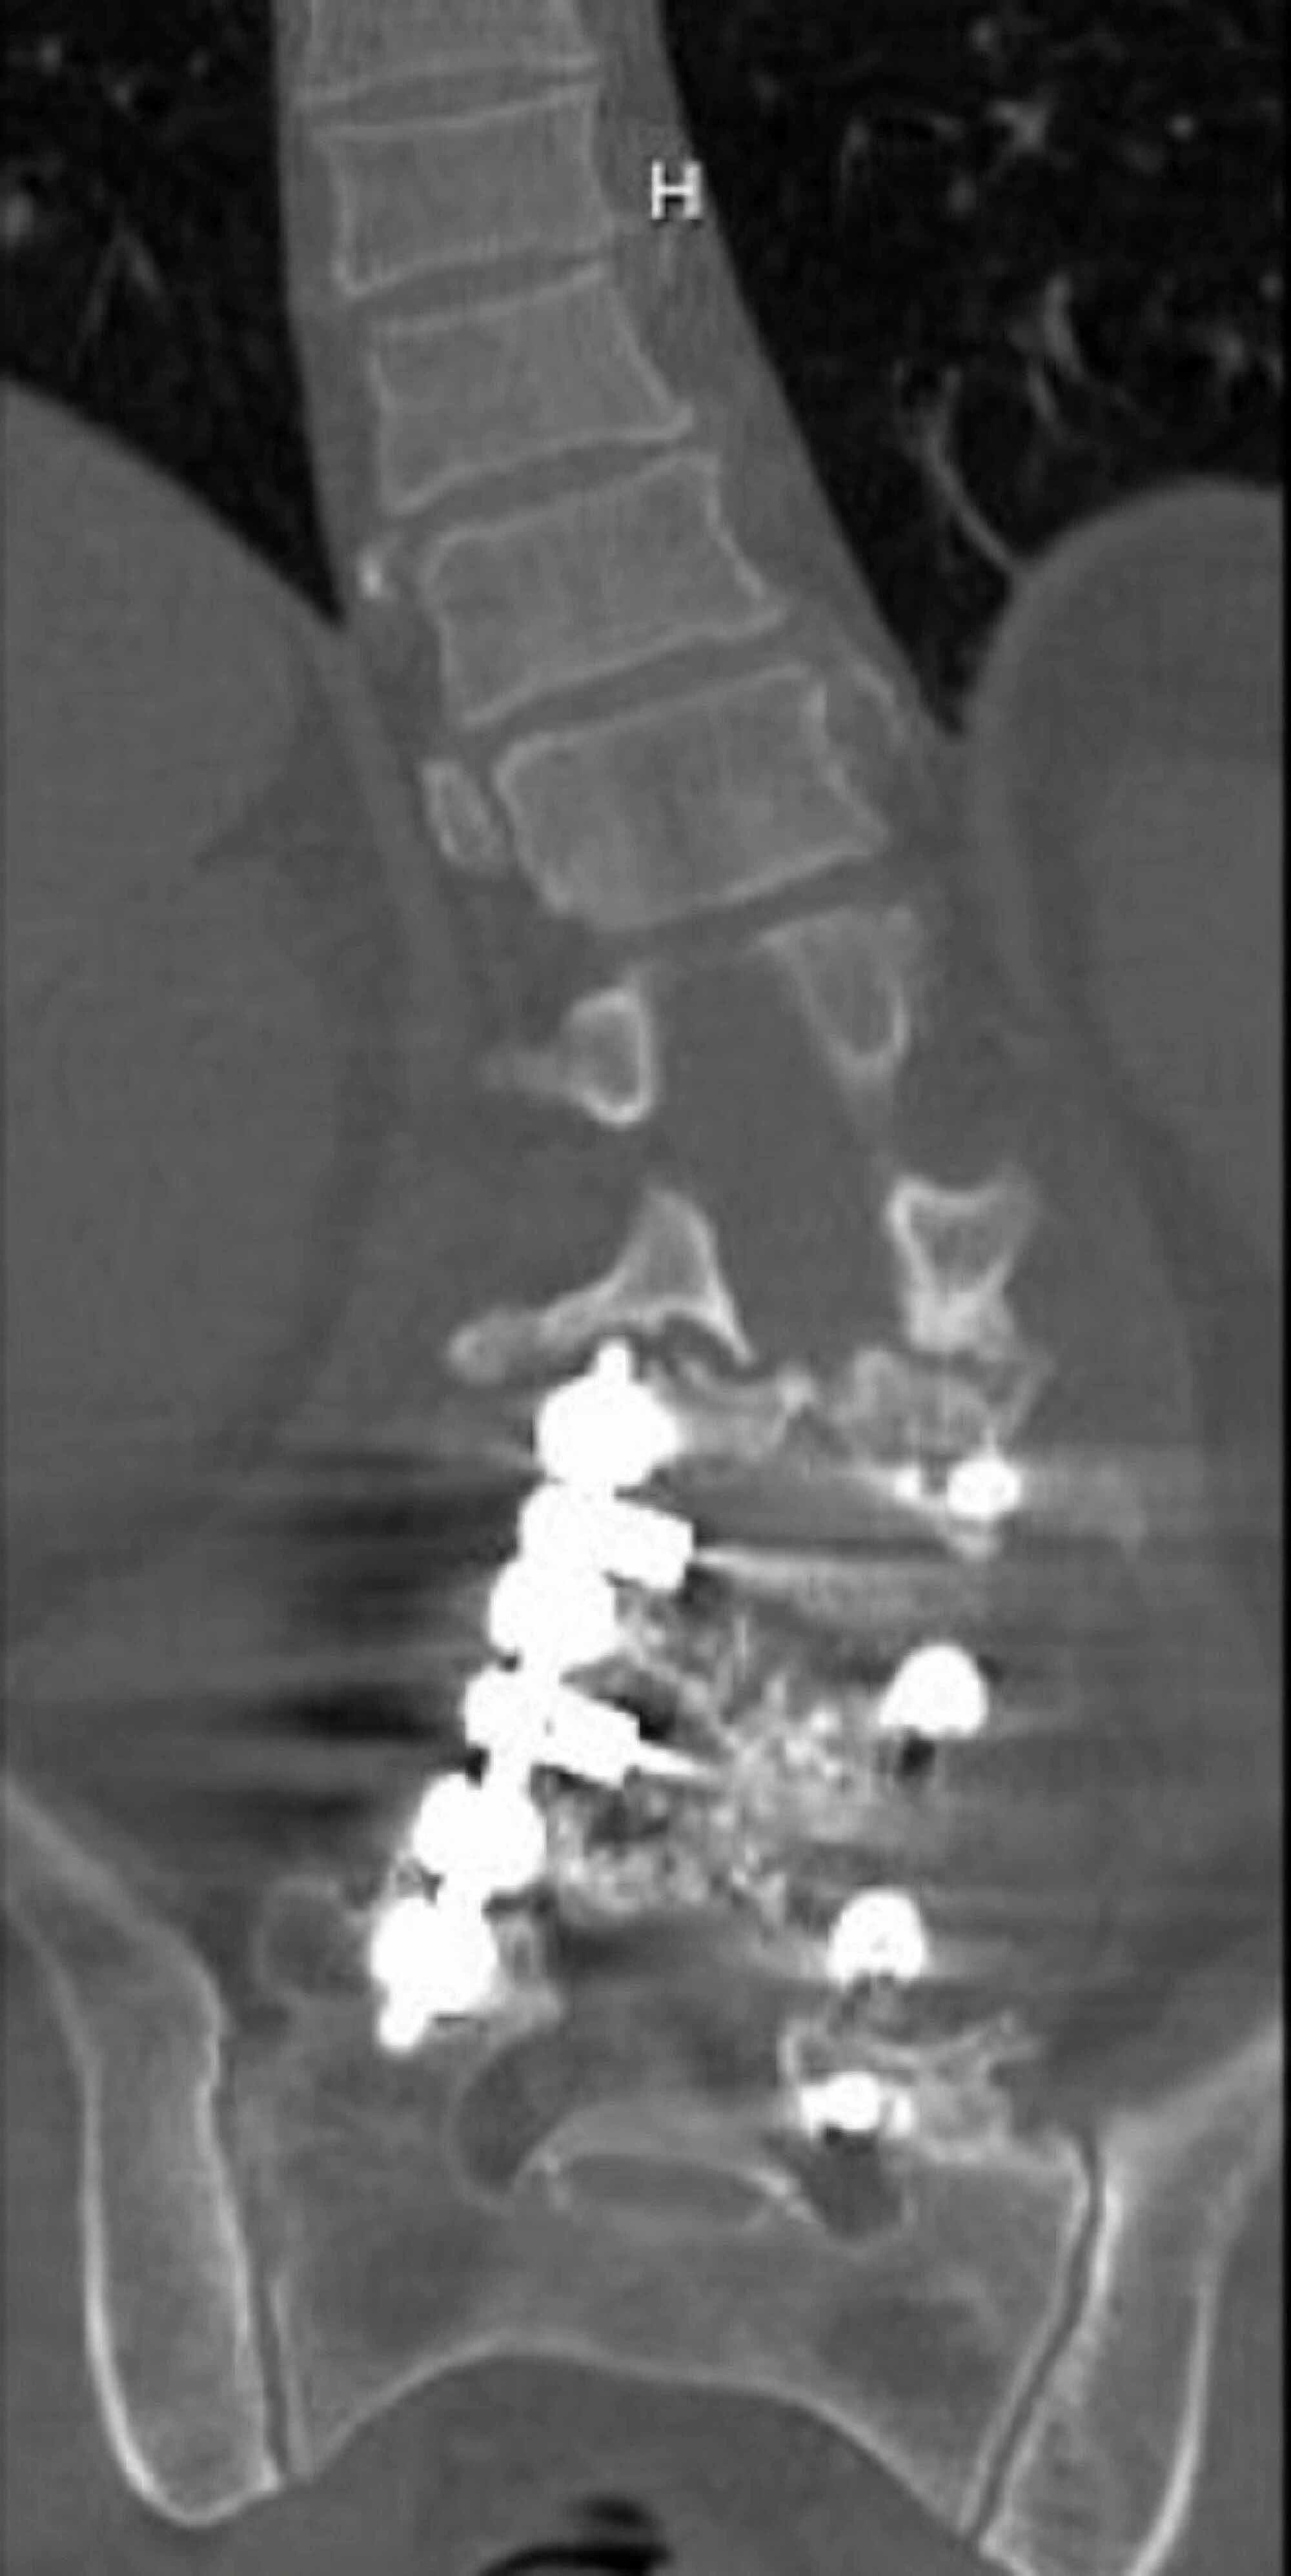

Case 4. This is a case of Type 2 CM. The kickstand rod technique Kickstand Rod The kickstand rod (kr) technique is powerful for correcting truncal shift. The kickstand rod spans the thoracolumbar junction proximally to the pelvis distally and is secured with an additional iliac screw placed. This study tested the hypothesis that the kr technique. The kickstand rod technique has been described as a novel technique for cm correction using an accessory rod on. Kickstand Rod.

Radiographs demonstrating the application of the kickstand rod Kickstand Rod This study tested the hypothesis that the kr technique. The kickstand rod technique has been described as a novel technique for cm correction using an accessory rod on the. The kickstand rod technique compares favorably with conventional techniques such as asymmetric osteotomies in cm. This technique was found to provide. New surgical procedure for correction of coronal imbalance (ci) in. Kickstand Rod.